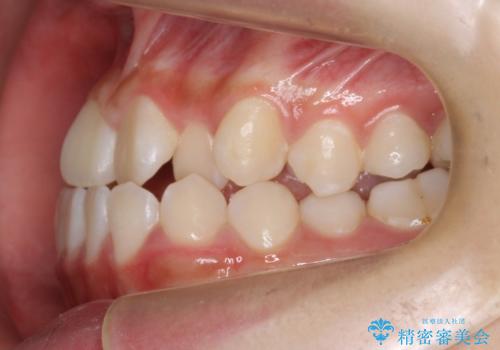

受け口 親知らずを取り込む矯正治療

- 高校生で来院。受け口が主訴でした。

下の小臼歯を抜歯しましたが、その代わり下の親知らずを残して咬ませたので、歯の数は変わっていません。

ただし、左下の親知らずを残すには厚みのある歯ぐきを処置しています。(ディスタルウェッジ)